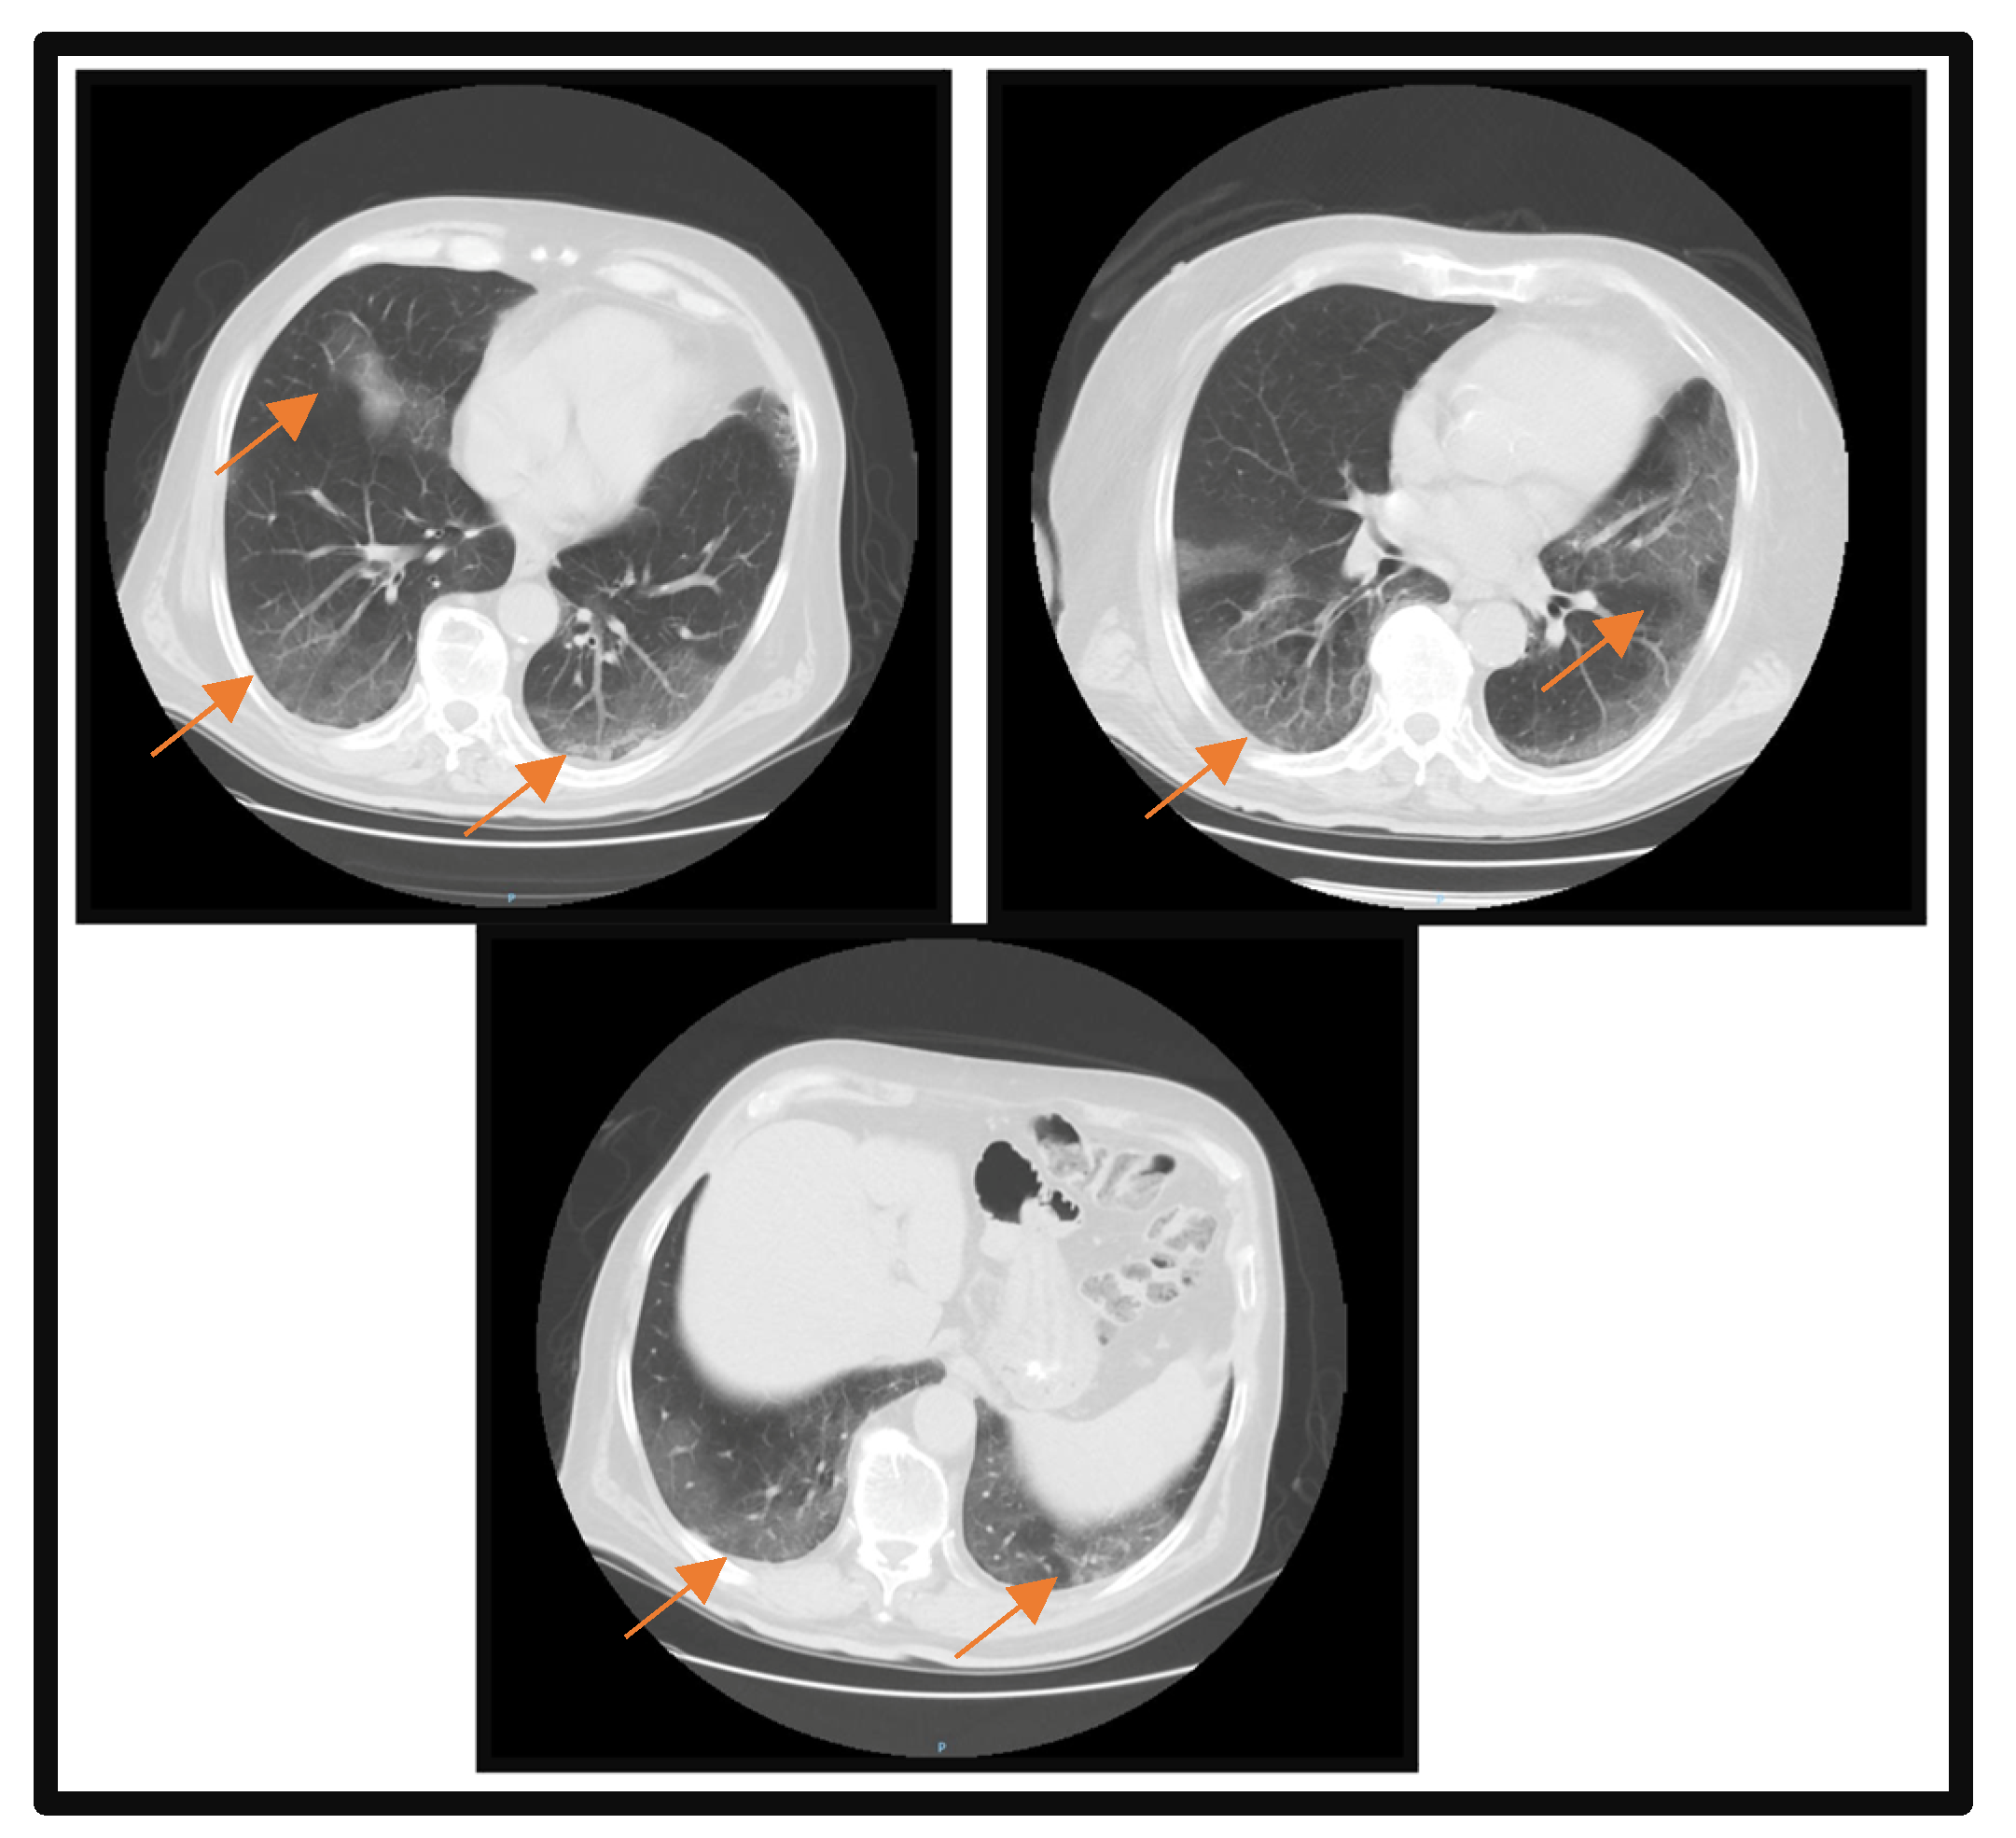

At the time of admission, a pulmonary computerized tomography (CT) scan was performed, which revealed multiple areas of condensation in the matt glass aspect disseminated bilaterally with fine left posterobasal interlobular septal thickening. A severity score of 10 out of 25 was reported; the lesions involved 5–25% of the right superior lobe, between 5 and 25% of the left middle lobe, 5 and 25% of the right lower lobe, 5 and 25% of the left superior lobe, and 5 and 25% of the left lower lobe (Figure 1). The severity score proposed by Francone M et al. was used to assess lung impairment [8]. Focal changes in centrilobular, panlobular, and paraseptal bilateral superior lobe emphysema, bilateral infrahilar bronchial ectasia, hiatal hernia of 33 × 28 mm, reduced stomach body size, more likely postoperative, with the appearance of a gastro-enteric anastomosis, and arranged paramedian left epigastric are also reported.

Figure 1.

Pulmonary CT scan at the time of admission. Orange arrows highlight the lesion areas of condensation in the matt glass aspect.